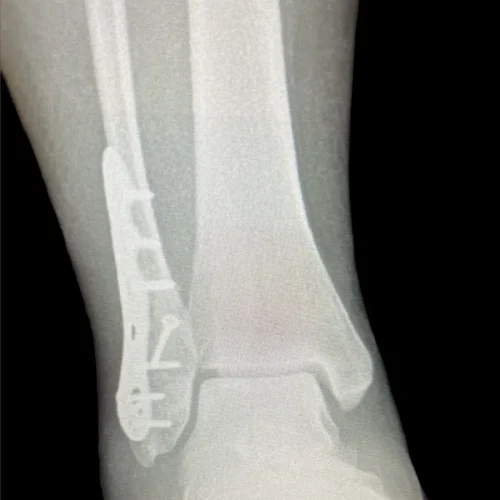

Surgical Intervention at Stepwell Institute is never a “one-size-fits-all” solution. We view surgery as a precise tool used to restore the natural biomechanics of the foot and ankle when non-invasive methods have reached their limit. Our philosophy centers on individualized surgical planning—using advanced imaging to map out the procedure before you ever enter the operating room. From correcting bunions and hammertoes to performing ligament repairs and fracture fixations, Dr. Yakov utilizes techniques designed to minimize trauma to the surrounding tissues, thereby reducing the risk of complications and ensuring a more stable, long-term result for our patients.

Stepwell Institute distinguishes itself by offering NJ patients access to the most advanced surgical modalities in modern podiatry. We specialize in Surgical Intervention, which utilize smaller incisions and specialized instruments to reduce post-operative pain and scarring. For more complex cases, we employ 3D-printed surgical guides and biological grafts to enhance the body’s natural healing ability. By choosing Stepwell Institute, you benefit from a specialized recovery plan where Dr. Yakov and our team prioritize early, safe mobilization. Our goal is to provide a definitive surgical solution that allows you to return to the active New Jersey lifestyle you love with confidence and strength. confidence and strength.

Our Case Study